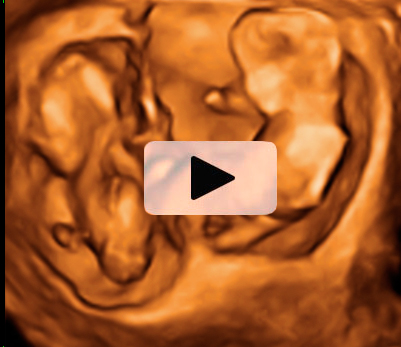

Ecografía Embarazo 2D y 3D Semana 12 - ANOMALIAS CROMOSÓMICAS